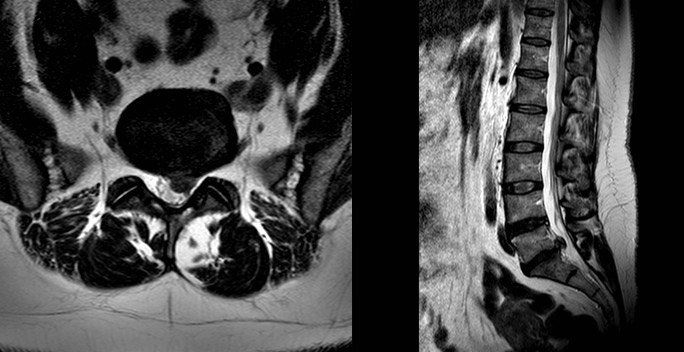

What does a disc prolapse look like?

In the back, disc prolapses are one of the most common findings. On MRI scan a prolapsed disc looks like a dark oval structure bulging into the spinal canal on the cross- section view. When it touches a nerve you will feel pain radiating from your back down the leg and this is known as sciatica.

The pictures above are of an MRI scan showing a prolapsed disc. The dark oval structure in the centre is a disc and the bulge coming off the base is the “prolapsed disc” protruding into the spinal canal on the cross- section view. In the image on the right the disc prolapse can be seen as a circle behind the spinal bones. When it touches a nerve you will feel pain radiating from your back down the leg and this is known as sciatica.